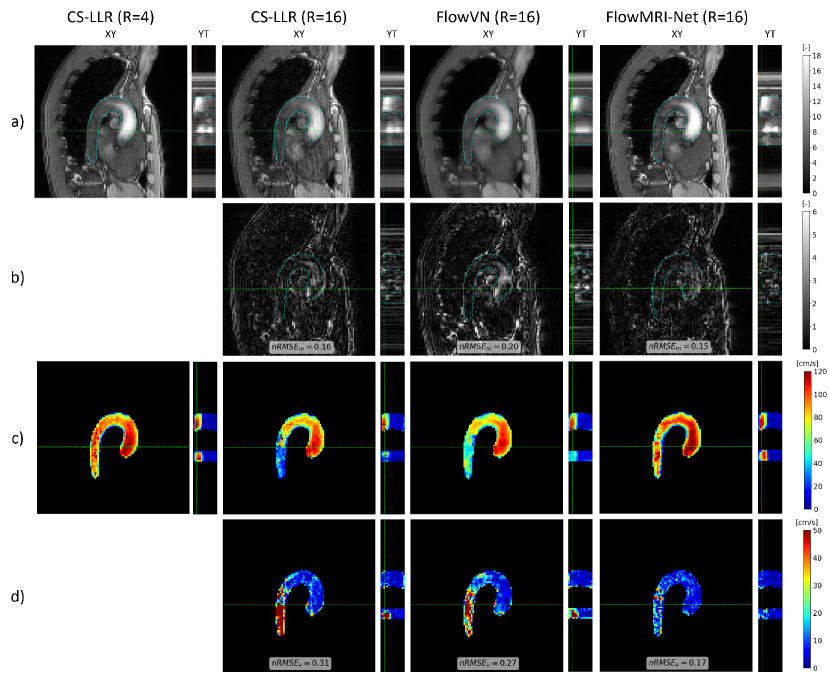

The quantitative metrics for aortic reconstructions using CS-LLR, FlowVN, and FlowMRI-Net are summarized in Table 2, with the image magnitudes, velocity magnitudes, and their errors of an exemplary healthy volunteer shown in Fig. 2 and 3 for 8-fold and 16-fold prospective undersampling, respectively. Visual image magnitude quality and values are similar for CS-LLR and FlowMRI-Net reconstructions for both undersampling factors, whereas FlowVN shows increased spatial and temporal blurring in the image magnitudes. Velocity magnitudes during peak systole are generally underestimated by CS-LLR and FlowVN, particularly in the descending aorta where SNR is lower due to the higher distance to the coils. This underestimation of velocity magnitude is reflected by the inferior and values of CS-LLR and FlowVN compared to FlowMRI-Net for both undersampling factors.

The superior reconstruction quality of prospectively undersampled aortic 4D flow MRI for R = 8 and 16 was demonstrated both qualitatively (Fig. 2 and 3) and quantitatively (Table 2), with FlowMRI-Net recovering more accurate structural details and hemodynamic features in the image magnitudes and velocity magnitudes compared to CS-LLR and FlowVN reconstructions, resulting in lower and values. Compared to the fully sampled 2D breath-hold scans, FlowMRI-Net accurately captures peak velocity in FH direction, as opposed to CS-LLR and FlowVN, which both underestimate peak velocity (Fig. 4). Velocities in RL and AP direction remain noisy, which can be explained by the relatively high venc = 150 cm/s compared to the maximum velocities that occur in those two directions for non-pathological flow (vmax ¡ 50 cm/s). The spatiotemporal blurring of FlowVN reconstructions in the work was not observed in the original paper [18], which may be explained by the change in training data and the switch from retrospectively-undersampled data with additional noise as input to prospectively-undersampled data. Also note that in the original paper the CS-LLR was not GPU-accelerated, hence the reported 30-fold increase in reconstruction speed, which does not hold anymore in this work as CS-LLR was also run on a GPU.